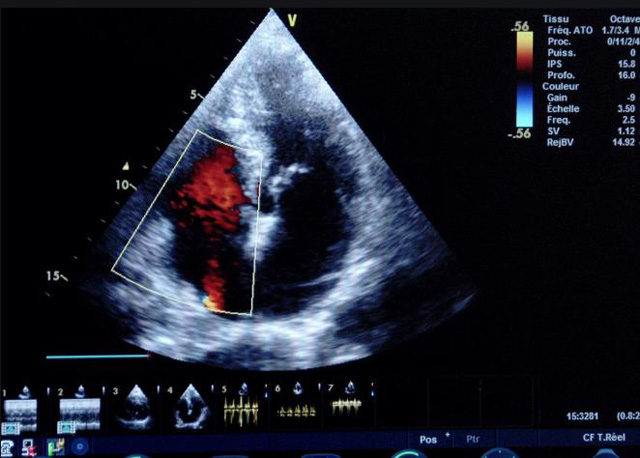

二、彩色室壁運動分析

(一)基本原理彩色室璧運動分析,從整體散射數(shù)據(jù)中識別心內(nèi)膜邊界,并與前一幀彩色不同,心臟收縮或舒張期開始到結(jié)束時心內(nèi)膜的全部過程。每一次順序顯示結(jié)束后,原來的彩色自動消失,以便進入下一個顯示過程。其結(jié)果是獲得對應(yīng)于每一個心動周期的彩色顯示,描繪特定周期內(nèi)室壁運動的時間運動軌跡。

(二)操作步驟根據(jù)背向散射數(shù)據(jù)中將心內(nèi)膜運動的位移過程分類為組織或血液的原理,邊緣檢測跟蹤心內(nèi)膜和血液的界面。橙色表示收縮期的開始,收縮期不同時相逐幀顯示色彩均疊加在收縮末期最后一幀圖像中。檢查時,可按以下步驟進行:

①顯示較為理想的二維圖像,常用切面有心尖四腔心、二腔心、左心室長軸和左心室乳頭肌水平短軸切面。

②啟動AQ系統(tǒng),啟動后適當?shù)卣{(diào)節(jié)增益補償,顯示心內(nèi)膜。

③啟動CK系統(tǒng),啟動后劃定感興趣區(qū)域。同時記錄的心動圖R波頂點為舒張末期,T波終點為收縮末期,顯示RT間期的CK彩階圖,連續(xù)記錄3~ 5個心動周期。

④對所獲圖像和數(shù)據(jù)進行分析和計算。

(三)檢測節(jié)段性室壁運動異常,研究冠心病患者左心室功能和分析局部室壁運動過程中。測量每一節(jié)段室壁的運動量,運動正常的節(jié)段彩帶色彩均勻?qū)哟喂庹_\動減弱的節(jié)段,厚度薄層次不全。心內(nèi)膜位移幅度和速度均減低。心內(nèi)膜位移幅度和速度甚低或難以測得。正常的多層彩帶消失,呈現(xiàn)紅色色帶,心內(nèi)膜位移呈負向,幅度和速度亦減低。急性心肌梗死的患者中可用于識別存活心肌抑或壞死心肌。多巴酚丁胺負荷試驗存活心肌的心內(nèi)膜位移幅度增高,停藥后即消失,而壞死心肌則無上述表現(xiàn)。實時檢查冠心病的節(jié)段性室壁運動異常,有時候通過發(fā)現(xiàn)局部心肌運動的時相異常,對于心臟傳導(dǎo)障礙的診斷也可能有幫助。